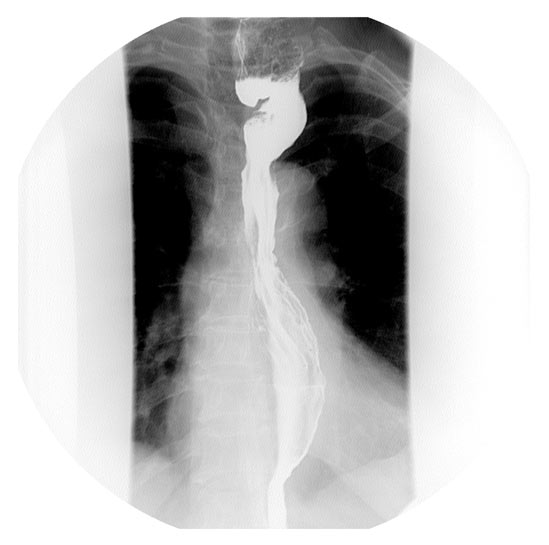

A 67 year old patient with a history of transhiatal esophagectomy (THE) and sub-sternal gastric pull-up ten years prior, at another institution, for early stage esophageal cancer presented with progressive dysphagia to solids. An initial esophagogastroduodenoscopy (EGD) found a large retained food bolus as well as tortuosity and dilatation of the cervical esophagus proximal to the esophagogastric anastomosis. No evidence of intrinsic anastomotic stricture or fibrosis was noted, but there was extrinsic compression. A barium esophagogram revealed significant extrinsic compression of the upper esophagus in the area of the anastomosis at the left clavicular head, with associated narrowing of the lumen and minimal transit of oral contrast (Figure 1). A computed tomography scan of the neck confirmed the sub-sternal location of the gastric pull-up within the anterior mediastinum, and revealed dilatation of the esophagus proximal to the anastomosis, with no associated masses or disease recurrence (Figure 2). The left sternoclavicular joint (SCJ) appeared to be compressing the conduit and was the point of obstruction.

To rule out anastomotic malignant recurrence, a flexible EGD was again performed with fluoroscopic guidance and four quadrant biopsies were taken off the distal cervical esophagus and the proximal gastric conduit. Fluoroscopy confirmed the intraluminal narrowing corresponded to the anatomic location of the left SCJ. The esophageal biopsies revealed squamous epithelium with no evidence of metaplastic, dysplastic, or neoplastic changes and the gastric conduit biopsies were benign as well. Given the absence of recurrent malignancy, the source of the extrinsic compression seen in the imaging of the patient’s cervical esophagogastric anastomosis was secondary to compression by her left SCJ. The patient elected to have the left SCJ resected due to ongoing worsening dysphagia.